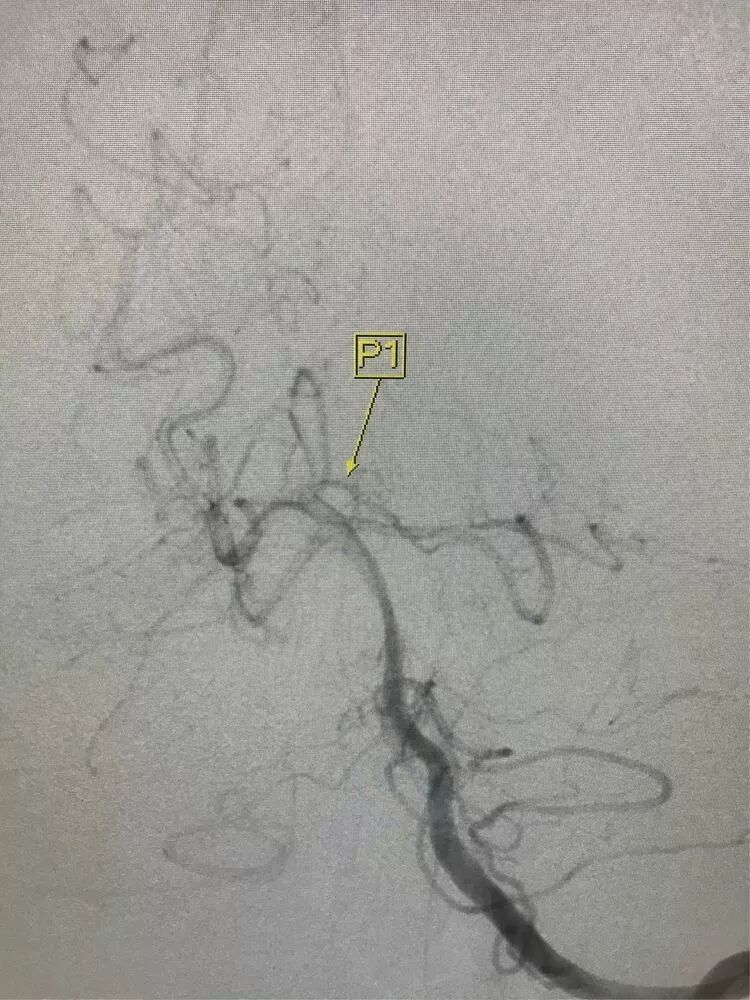

男,49岁,蛛网膜下腔出血

左侧后交通动脉瘤,胚胎型大脑后动脉

3D

局部观,宽颈,涉及颈内动脉和后交通动脉

椎动脉造影见左侧大脑后动脉P1段很细

栓塞的关键是既要保持颈内动脉通畅,又要保持后交通动脉通畅。双导管单纯填塞;通过颈内动脉释放支架灯笼技术辅助是可选的方案。本例是通过后交通动脉释放支架,利用支架摆尾技术(half-T)来进行栓塞。支架导管塑型